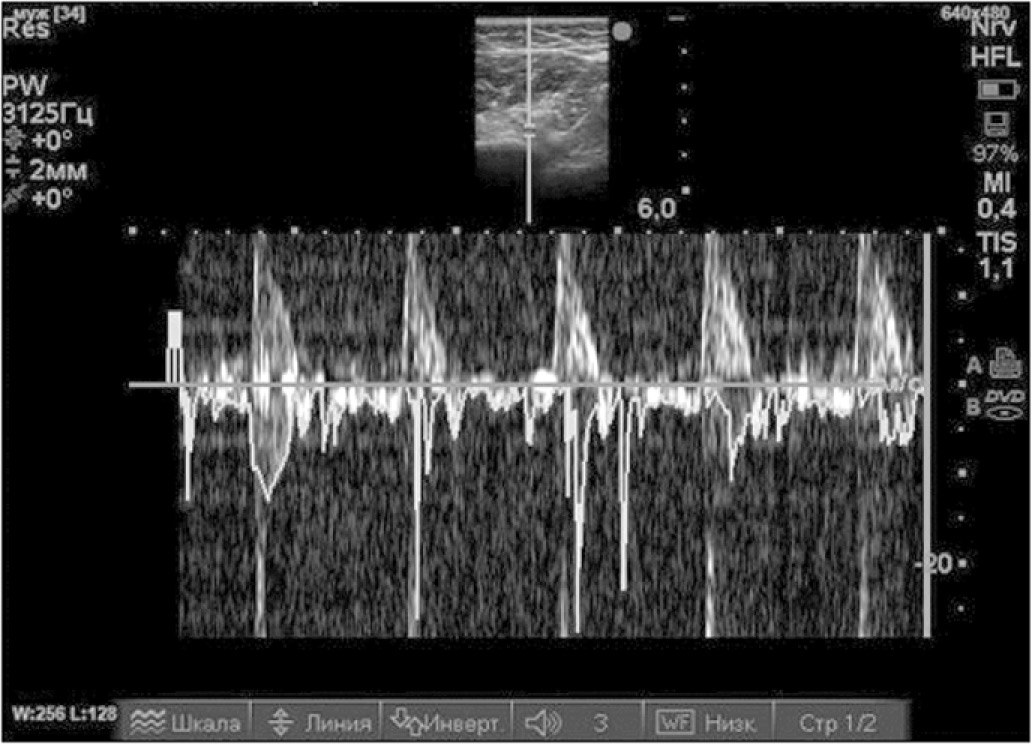

Затем, не меняя положения пациента, датчик переводили в горизонтальную плоскость в область хирургической шейки плечевой кости, добиваясь продольной визуализации задней огибающей плечо артерии и сопровождающего её подмышечного нерва (рис. 5). Идентифицировали место выхода подмышечного нерва из четырёхстороннего отверстия (рис. 6), который здесь отдает суставные ветви. Иглу вводили латеральнее датчика по длинной оси в вентро-медиальном направлении и инъецировали 5 мл 0,75% раствора ропивакаина до появления гипоэхогенной тени вокруг нерва и прекращения нейростимуляционных сокращений дельтовидной мышцы. Эффективность блокады надлопаточного и подмышечного нервов оценивали по невозможности отведения и поднятия блокируемой конечности при сохранении движений в локтевом суставе и кисти.

Рис. 5. Поперечное сканирование при включенном PW (импульсно-волновом) допплере. Идентифицирована задняя огибающая плечо артерия в месте её отхождения от подмышечной артерии